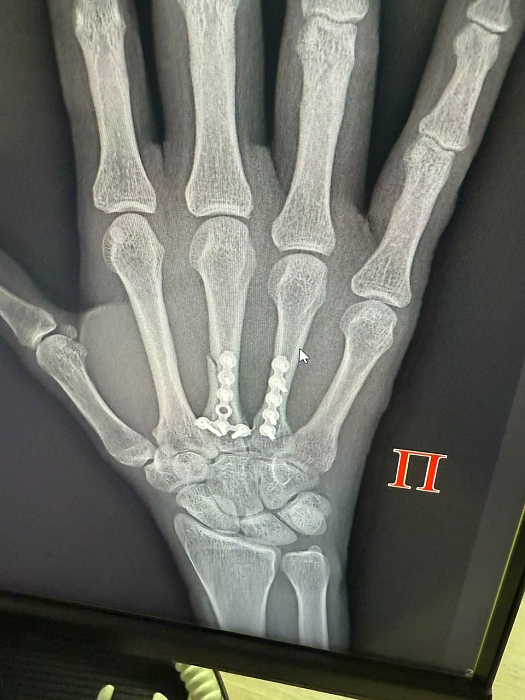

Остеосинтез кости запястья

Патологиями области лучезапястного сустава занимается кистевой хирург. При поражении костей запясться он выполнит процедуру остеосинтеза.